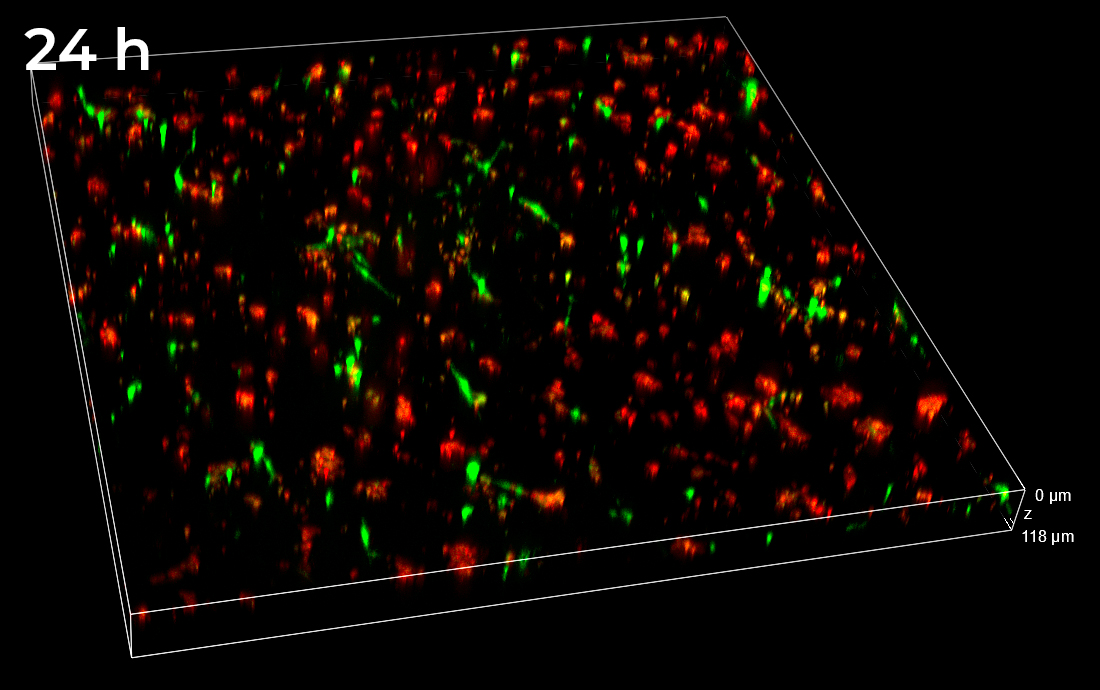

In the Figure 2, the full field of view (FOV) in XYZ dimensions collected 24 h post-treatment is shown. Thanks to the 25 mm diagonal FOV of the camera and to the ability to penetrate inside the sample without losing the spinning disk confocality, it was possible to visualize and record cells that homogeneously colonize the entire thickness of the 3D matrix.

Figure 2. 3D view of the entire FOV acquired with spinning disk at 24 h post-treatment. FOV with XY=4422×4422 µm, Z=530 µm. 3D matrix thickness was entirely acquired. Tumor target A673 cells are shown in red and AD-MSCs TRAIL in green.

Data obtained from live monitoring of co-cultures in VITVO were compared with end-point readouts from fixed samples at specific time points post-treatment (24 and 72 h, Figure 8). 3D comparison among three different FOVs confirmed a homogeneous distribution of cells without any significant inter-field difference. These data point out that AD-MSCs TRAIL were persisted over time, instead of A673 tumor cells which massively decreased in their signal and cell density (Figure 8).

Figure 8. Z-stacks on VITVO FOVs collected and fixed at different time points with spinning disk. 3 different FOVs corresponding to 24 h and 72 h post-treatment fixed sample, respectively (10x objective magnification).